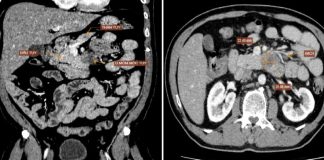

Phát hiện mắc loại UT có tỷ lệ t:ử v:ong cao...

Những dấu hiệu bất thường trên cơ thể có thể là dấu hiệu cảnh báo ung thư. Bệnh nhân N.V.Đ, trú tại Hà Nội, đi khám trong tình trạng đau vùng thượng vị suốt hai tháng, cơn đau lan ra sau lưng và ngày càng dữ dội. Kết quả siêu âm tại MEDLATEC ghi nhận [...]